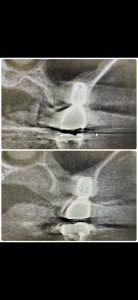

次は下6番の根充、4ヶ月経過

これも大したインパクトは無いが、昨年から大臼歯には白水のエンドシェーパー、グライダーを拘り使用

モリタの専用コントラ、800回転 1Nで使用

非常に楽、特に上のエンド3角、湾曲根管にはベスト

是非、使ってもらいたい‼️

手用では限界あり、治療成績にムラが出るからね